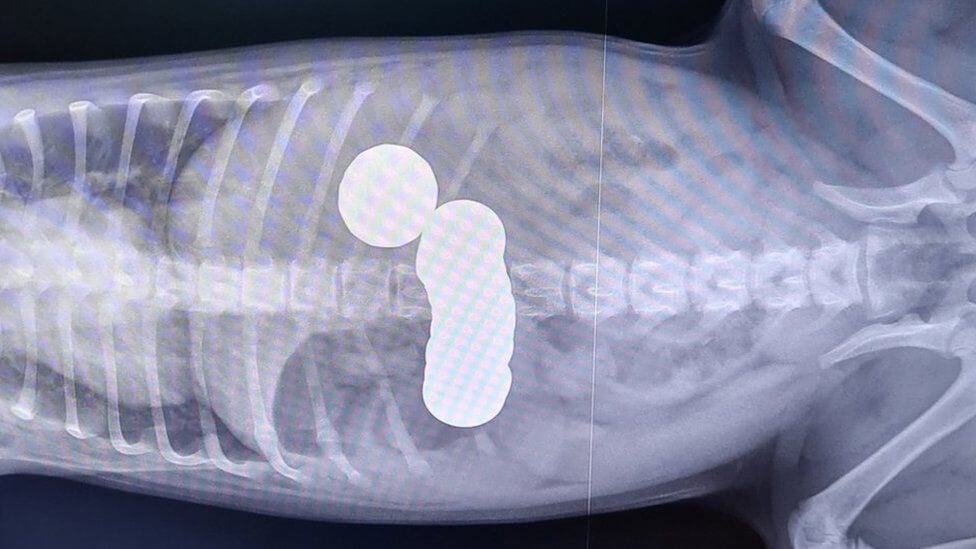

De acordo com a ONG PDSA, Ivana, a tutora da Daisy, ficou preocupada quando a cachorrinha começou a vomitar e parou de comer. Assim, ela a levou ao veterinário, onde imagens de raio X mostraram que o cachorro havia engolido 20 moedas.

Durante os exames, os veterinários viram que era o estômago que estava causando muita dor ao cachorrinho. Ao ver a moeda, levantaram suspeitas de um bloqueio, então ela foi sedada e radiografada. Felizmente, a operação foi um sucesso e Daisy pôde ir para casa no dia seguinte, apenas com medicamentos.

A enfermeira veterinária Sally Frith também conta que não conseguia acreditar na quantidade de moedas ingeridas, principalmente por um cachorro tão pequeno. “As moedas estavam causando um bloqueio que, se fossem deixadas, poderiam ter sido fatais, então é bom que sua tutora a trouxe para cá. Daisy voltou para fazer check-ups e estamos satisfeitos por ela estar se recuperando e se curando bem”, finalizou a enfermeira em entrevista ao BBC.